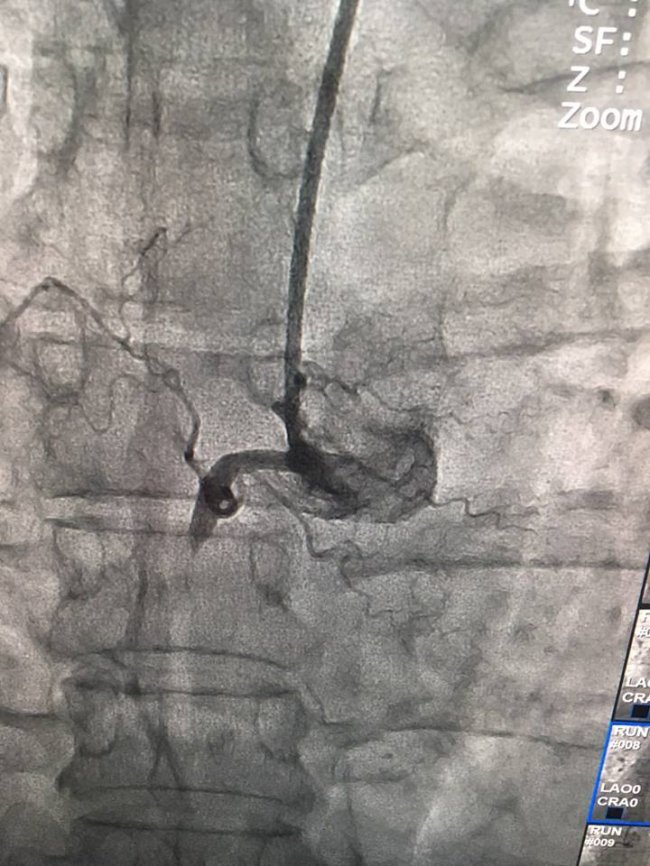

"Сьогодні нашими лікарями за допомогою сучасного ангіографа урнентно проведено стентування коронарних артерій хворому П. з приводу інфаркту міокарда.

Врятоване ще одне життя!!!",- йдеться в дописі.